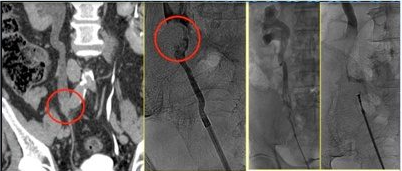

Un altro esempio è rappresentato dalla biopsia endoureterale, che può essere eseguita:

- per via discendente, entrando dalla cute nel rene e successivamente nell’uretere

Biopsia endoureterale